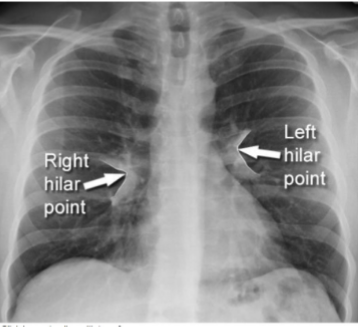

Idenfity R + L hila

yes